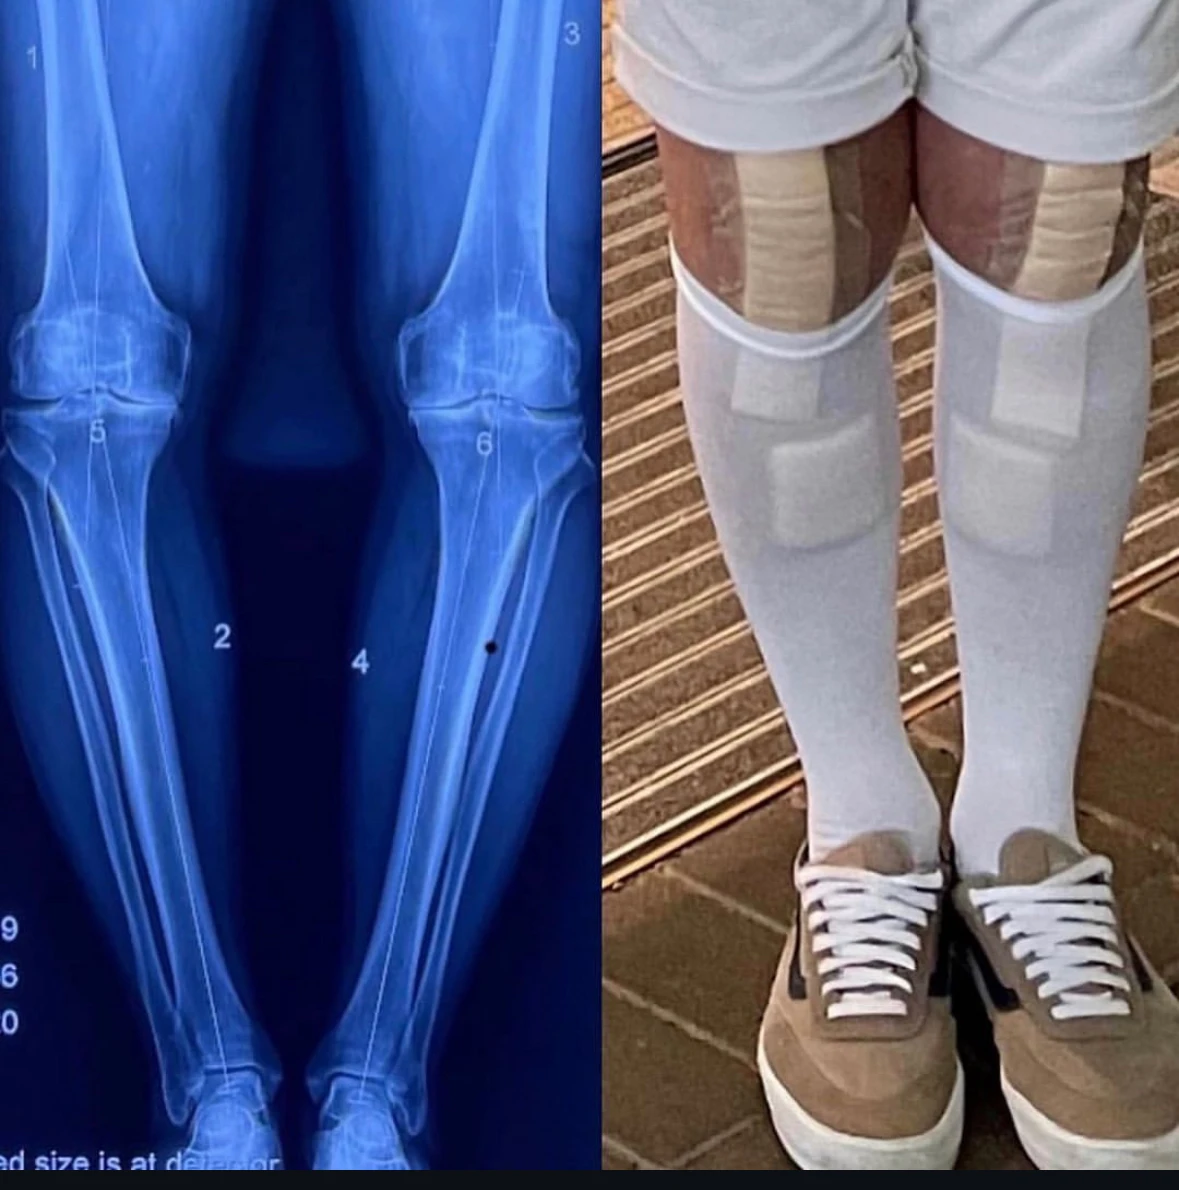

Patient at Sports and Spine Physiotherapy in Brookvale - Northern Beaches undertaking post surgery rehab after knee surgery